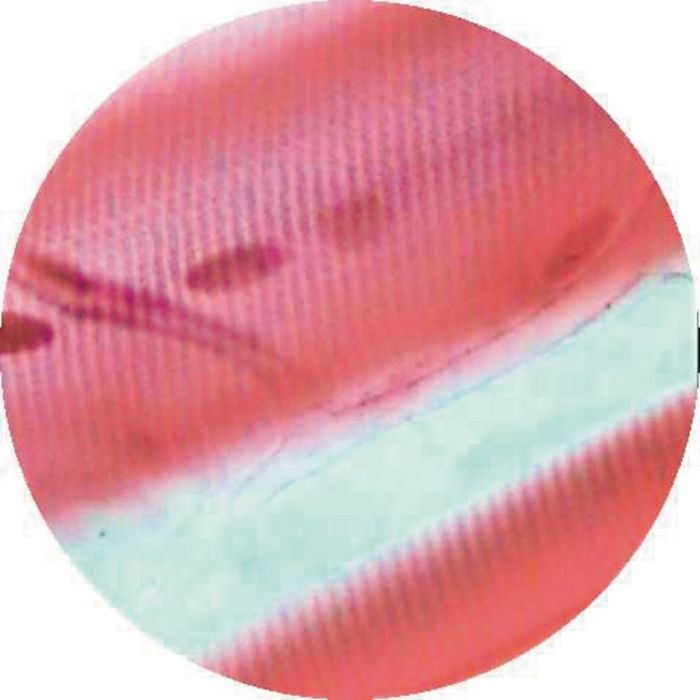

Cardiac muscle, I.s. for intercalculated discs.